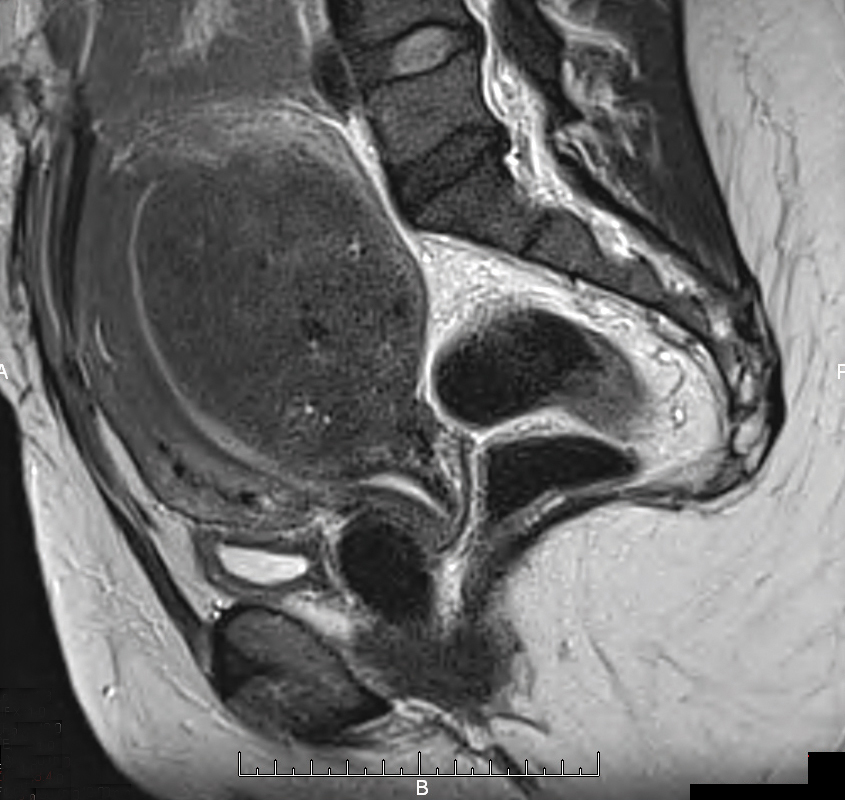

Il s'agit d'une adénomyose diffuse corporéale postérieure. Épaississement de la zone jonctionnelle transversale. Imagerie pelvienne par résonance magnétique, coupe sagittale en séquence T2. Sur le plan clinique, l'adénomyose est souvent asymptomatique. Chez les femmes symptomatiques, les ménorragies, présentes dans 50 % des cas, sont le symptôme le plus fréquent, mais leur incidence n'est pas corrélée à la profondeur de l'envahissement du myomètre. L'IRM permet de distinguer l'adénomyose sous-endométriale, l'adénomyose focale, appelée aussi adénomyome, et l'adénomyose diffuse. Mais la référence pour le diagnostic d'adénomyose est l'examen anatomo-pathologique.